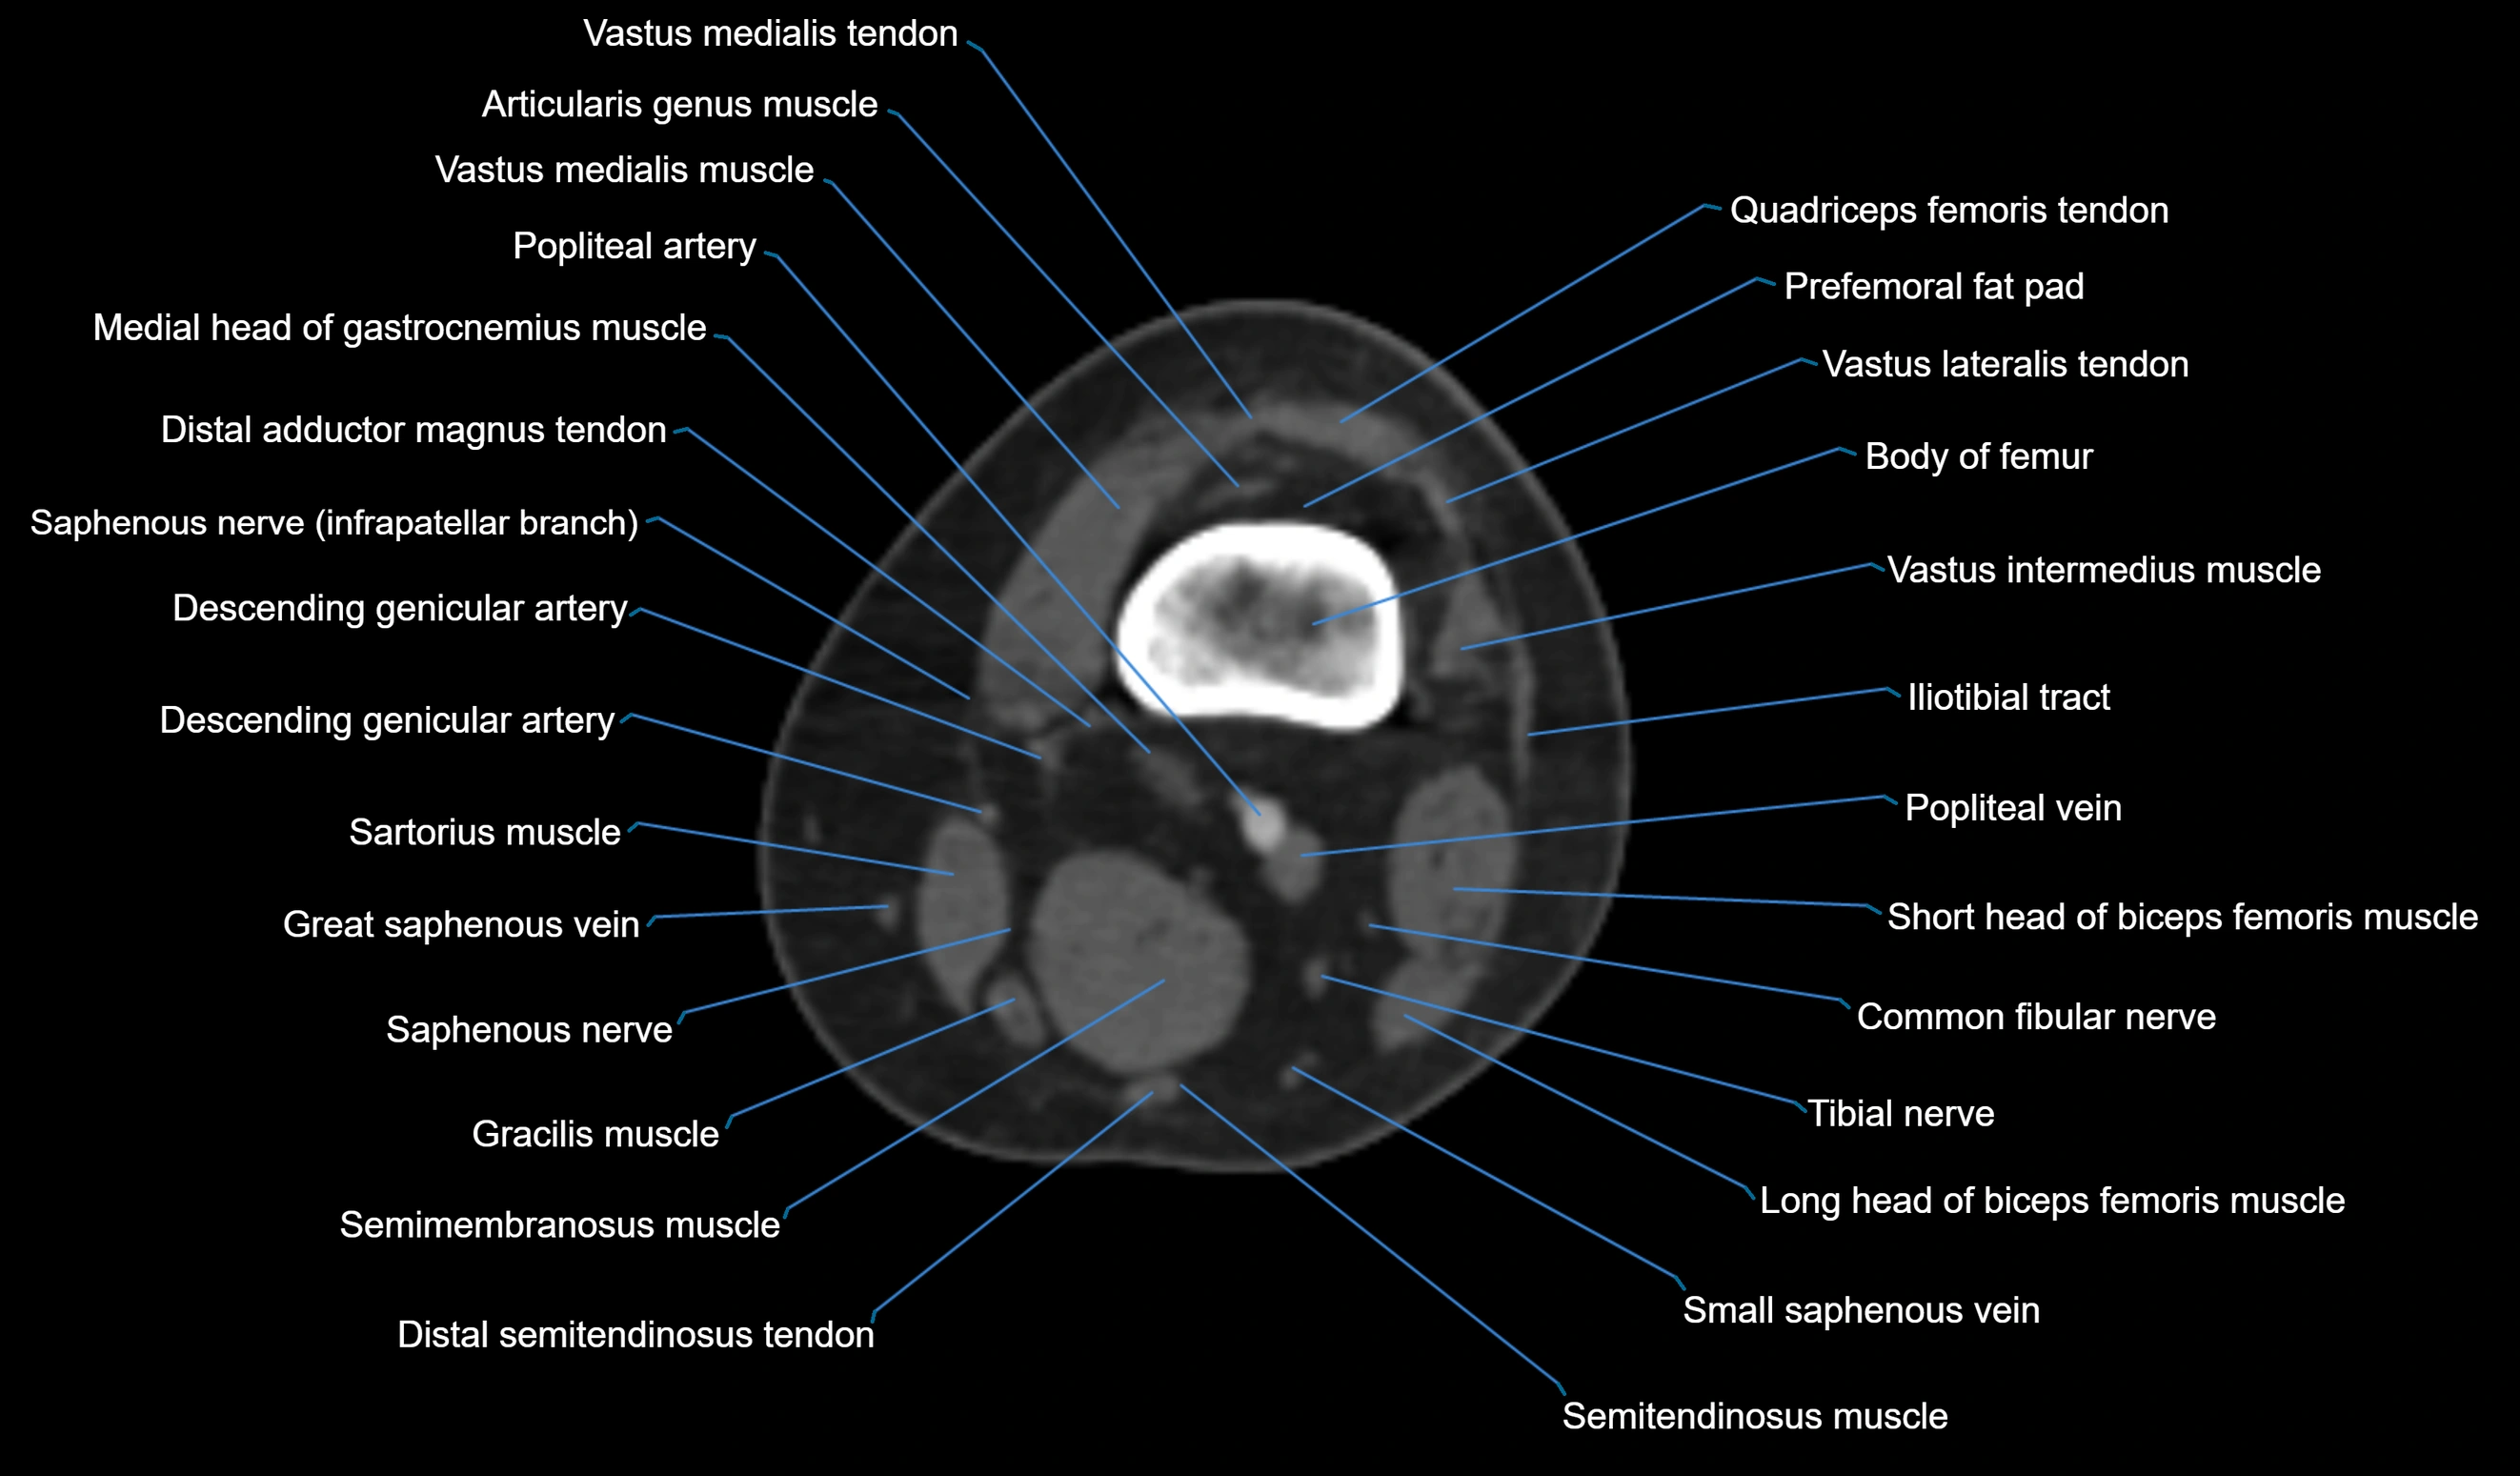

- Body of femur

- Distal adductor magnus tendon

- Distal quadriceps femoris tendon

- Distal vastus intermedius tendon

- Distal vastus lateralis tendon

- Distal vastus medialis tendon

- Lateral head of gastrocnemius muscle

- Medial head of gastrocnemius muscle

- Plantaris muscle

- Popliteal artery

- Popliteal vein

- Prefemoral fat pad

- Sartorius muscle

- Semimembranosus muscle

- Semitendinosus muscle

- Small saphenous vein

- Tibial nerve

- Vastus lateralis muscle

- Vastus medialis muscle